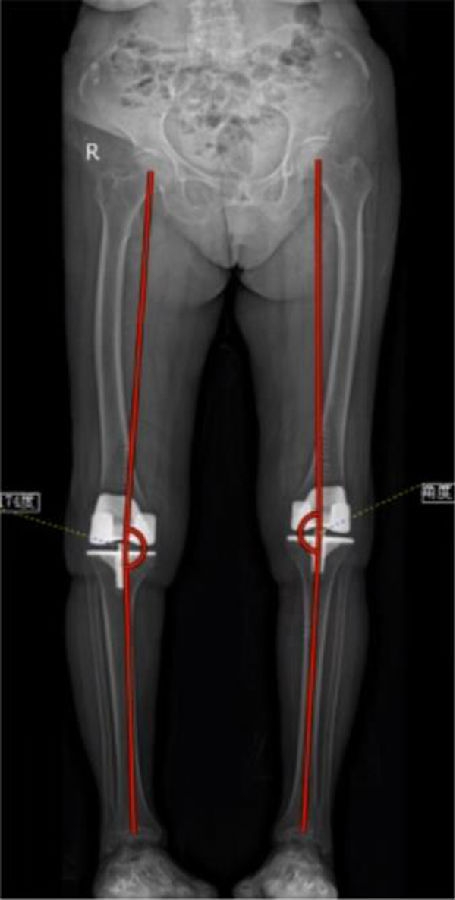

arKA组术后HKAA、cTCA明显小于aMA组,arKA组cFCA明显大于aMA组,差异均有统计学意义(p<0.05)。

图14 下肢力线(R)